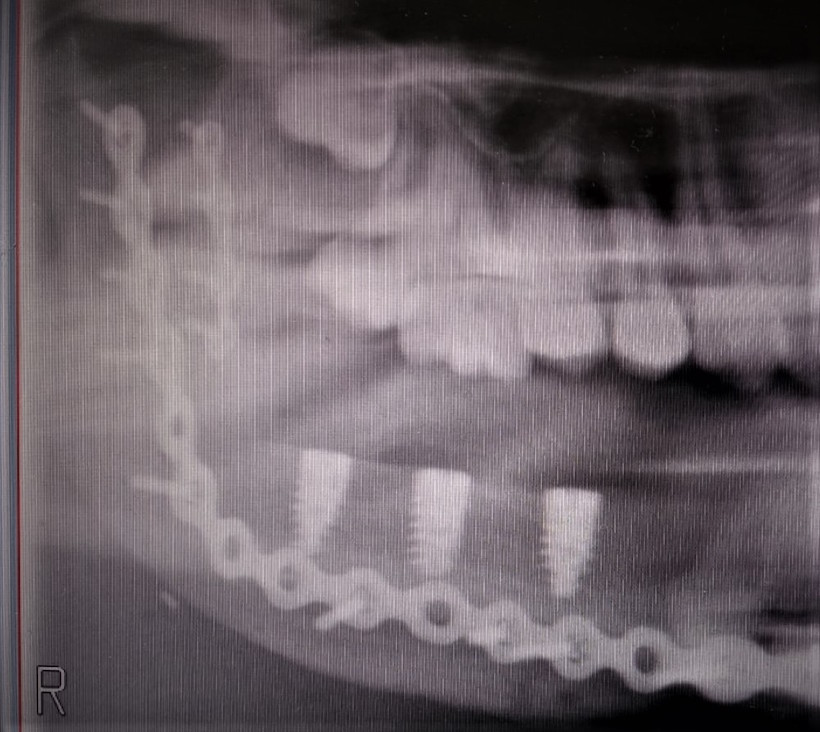

Pacjentka lat 15, zgłosiła się do poradni chirurgii szczękowo - twarzowej Szpitala Specjalistycznego im. L. Rydygiera w Krakowie z powodu rozległego guza trzonu, kąta i gałęzi żuchwy po stronie prawej. Na wykonanym zdjęciu ortopantomograficznym (OPG) uwidoczniono rozległy wielokomorowy ubytek kości żuchwy z całkowicie zatrzymanym zębem 46 w jego świetle oraz zepchnięciem zębów 47,48 w kierunku gałęzi żuchwy (Fig. 1.). W badaniu tomografii komputerowej uwidoczniono guz zniekształcający kość żuchwy po stronie prawej z jej rozdęciem i niszczeniem blaszki korowej od strony zewnętrznej oraz wewnętrznej (Fig. 2.). Wynik badania histopatologicznego pobranych wycinków z guza potwierdził rozpoznanie szkliwiaka (typ pęcherzykowo-akantomatyczny).

Fig.1. Zdjęcie OPG 15-letniej chorej – charakterystyczny obraz radiologiczny szkliwiaka w zakresie trzonu oraz kąta żuchwy po stronie prawej z całkowicie zatrzymanym zębem 46, powodujący przemieszczenie zębów 47,48 w kierunku gałęzi żuchwy

W okresie pooperacyjnym nie stwierdzono powikłań w gojeniu ran pooperacynych. W wykonanych badaniach tomografii komputerowej części twarzowej czaszki (Fig. 21.) oraz OPG (Fig. 22.) potwierdzono poprawność rekonstrukcji żuchwy oraz prawidłową pozycję jednoczasowo założonych implantów. Po upływie 6 miesięcy od wykonanego zabiegu chirurgicznego i pełnym zrośnięciem się kikutów żuchwy z płatem mikrochirurgicznym z talerza kości biodrowej oraz osteointegracji implantów zębowych z przenoszonym fragmentem kostnym w chorej planowane są dalsze etapy leczenia implantoprotetycznego.

Fig. 22. Kontrolne zdjęcie OPG z widocznymi założonymi 3 implantami Alpha Bio MultiNeo CS